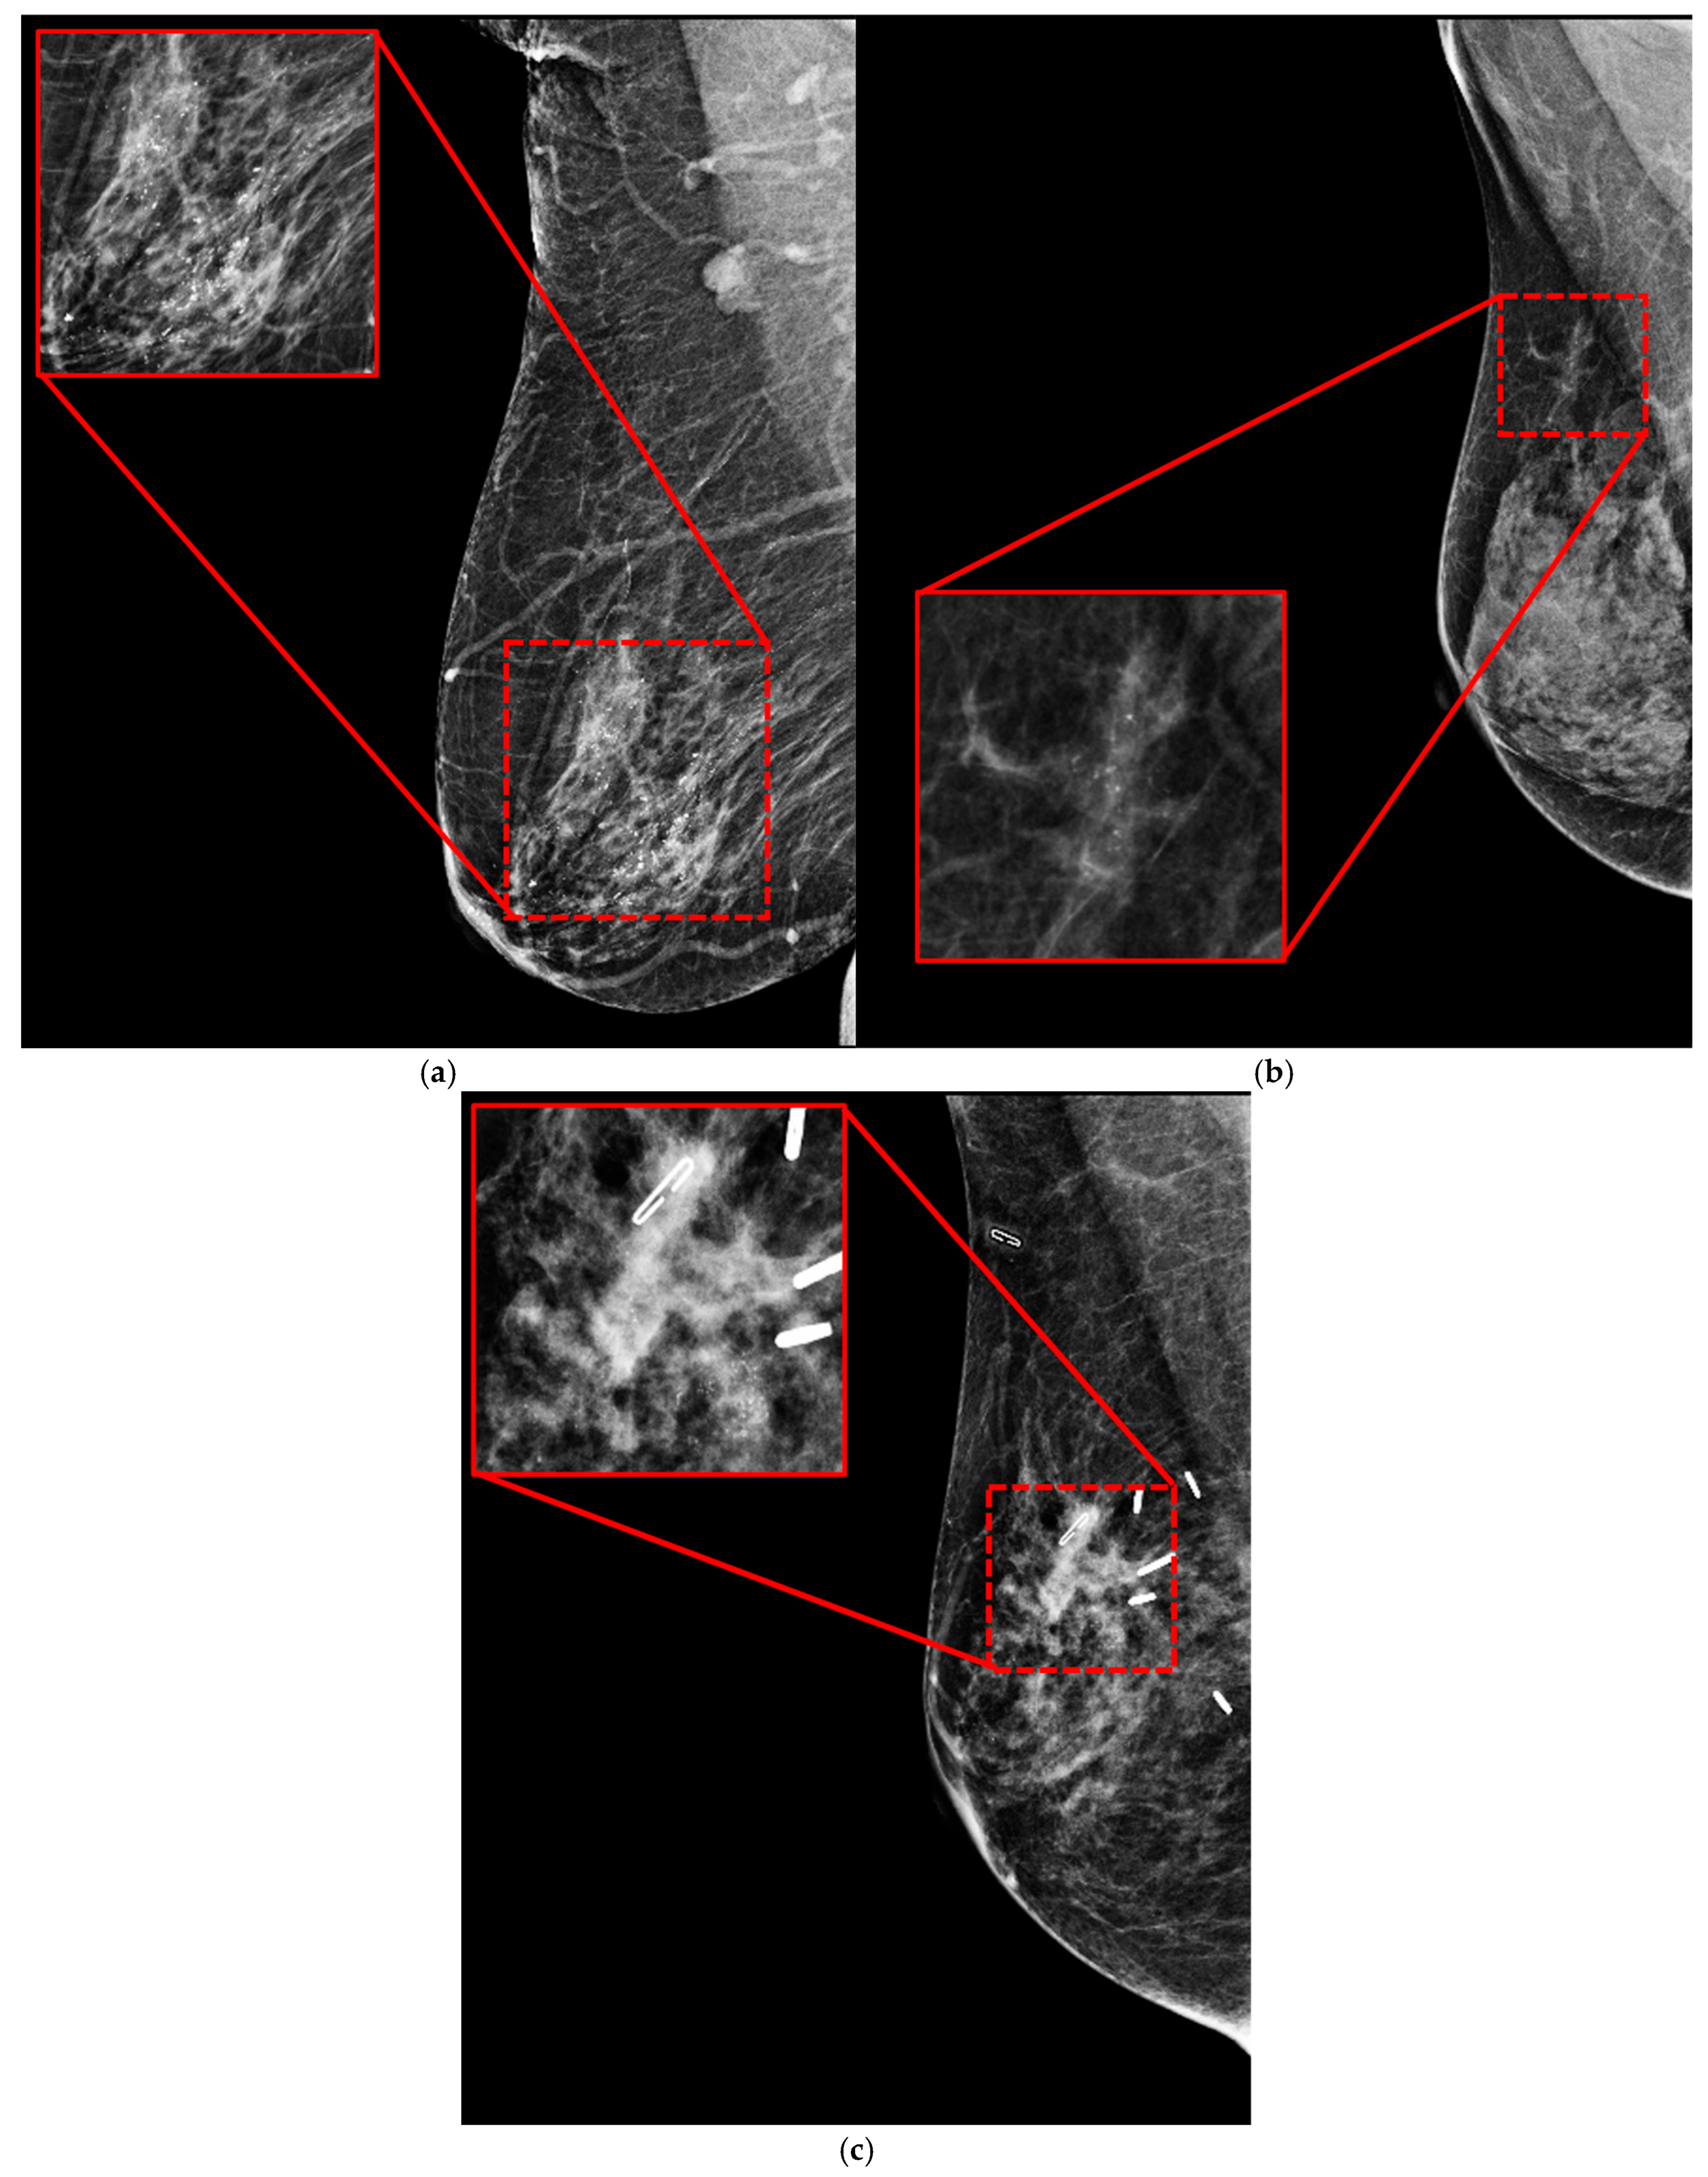

3.2. Mammogram Dataset

3.2.1. Private Dataset

- Berment, H.; Becette, V.; Mohallem, M.; Ferreira, F.; Chérel, P. Masses in mammography: What are the underlying anatomopathological lesions? Diagn. Interv. Imaging 2014, 95, 124–133. [Google Scholar] [CrossRef]

- Hernández, P.A.; Estrada, T.T.; Pizarro, A.L.; Cisternas, M.D.; Tapia, C.S. Breast calcifications: Description and classification according to bi-rads 5th edition. Rev. Chil. Radiol. 2016, 22, 80–91. [Google Scholar]

- Kim, S.; Tran, T.X.M.; Song, H.; Park, B. Microcalcifications, mammographic breast density, and risk of breast cancer: A cohort study. Breast Cancer Res. 2022, 24, 96. [Google Scholar] [CrossRef]